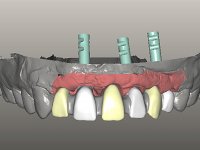

Foi aconselhada a extracção dos dentes 12 e 11 e esperar mais 3 meses para se conseguir uma completa cicatrização da zona. Estabilizada a situação fazer-se –ia um enceramento de diagnóstico que dando origem a uma guia imagiológica permitiria fazer uma TAC. em que o posicionamento idealizado dos dentes pudesse ser relacionado com o património ósseo. O objectivo seria fazer uma ponte cerâmica implanto suportada.

O paciente foi observado conjuntamente e a dúvida que surgiu de imediato foi se seria possível com a regeneração óssea a efectuar poder ser reabilitada naturalmente a zona das papilas interdentárias. Nesse sentido foi feito um enceramento de diagnóstico que contemplaria as duas hipóteses, utilizando ou não a cerâmica gengival. A confecção desse enceramento foi fundamental para expor ao paciente a dificuldade da reabilitação. O wax-up deu origem a um mock-up que foi aprovado pelo paciente e que simultaneamente serviu de guia imagiológica. O caso foi planificado cirurgicamente e realizada uma guia cirúrgica com que foram colocados os implantes. Após 10 semanas foi feita a 1ª impressão para confecção da ponte provisória. Foram criados os primeiros perfis de emergência na gengiva artificial e foi digitalizado o modelo. Por processo de CAD-CAM foi confeccionada uma ponte provisória aparafusada baseada no enceramento de diagnóstico. A ponte trabalhou durante 8 semanas os tecidos moles que foram fielmente copiados numa impressão com técnica de moldeira aberta. Os transferes foram individualizados com resina composta para copiarem fielmente os perfis de emergência criados pela ponte provisória. Confeccionado o modelo de trabalho definitivo, foi realizada uma infra-estrutura em zircónio seguindo a orientação do enceramento de diagnóstico. O assentamento da infra-estrutura foi testado em boca e simultaneamente foi novamente impressionados os tecidos moles com um silicone fluido. Nessa consulta foi feito o levantamento da cor. Os dentes 13 e 23 apresentavam uma saturação anormalmente forte que resolvemos não valorizar, optando por privilegiar a relação com o sector antero-inferior. Foi realizada uma nova gengiva artificial com a impressão que acompanhou a impressão de arrasto com a infra-estrutura. Após a colocação da cerâmica na infra-estrutura foram coladas as meso-estruturas. O trabalho final foi aparafusado lentamente permitindo a adaptação dos tecidos moles.